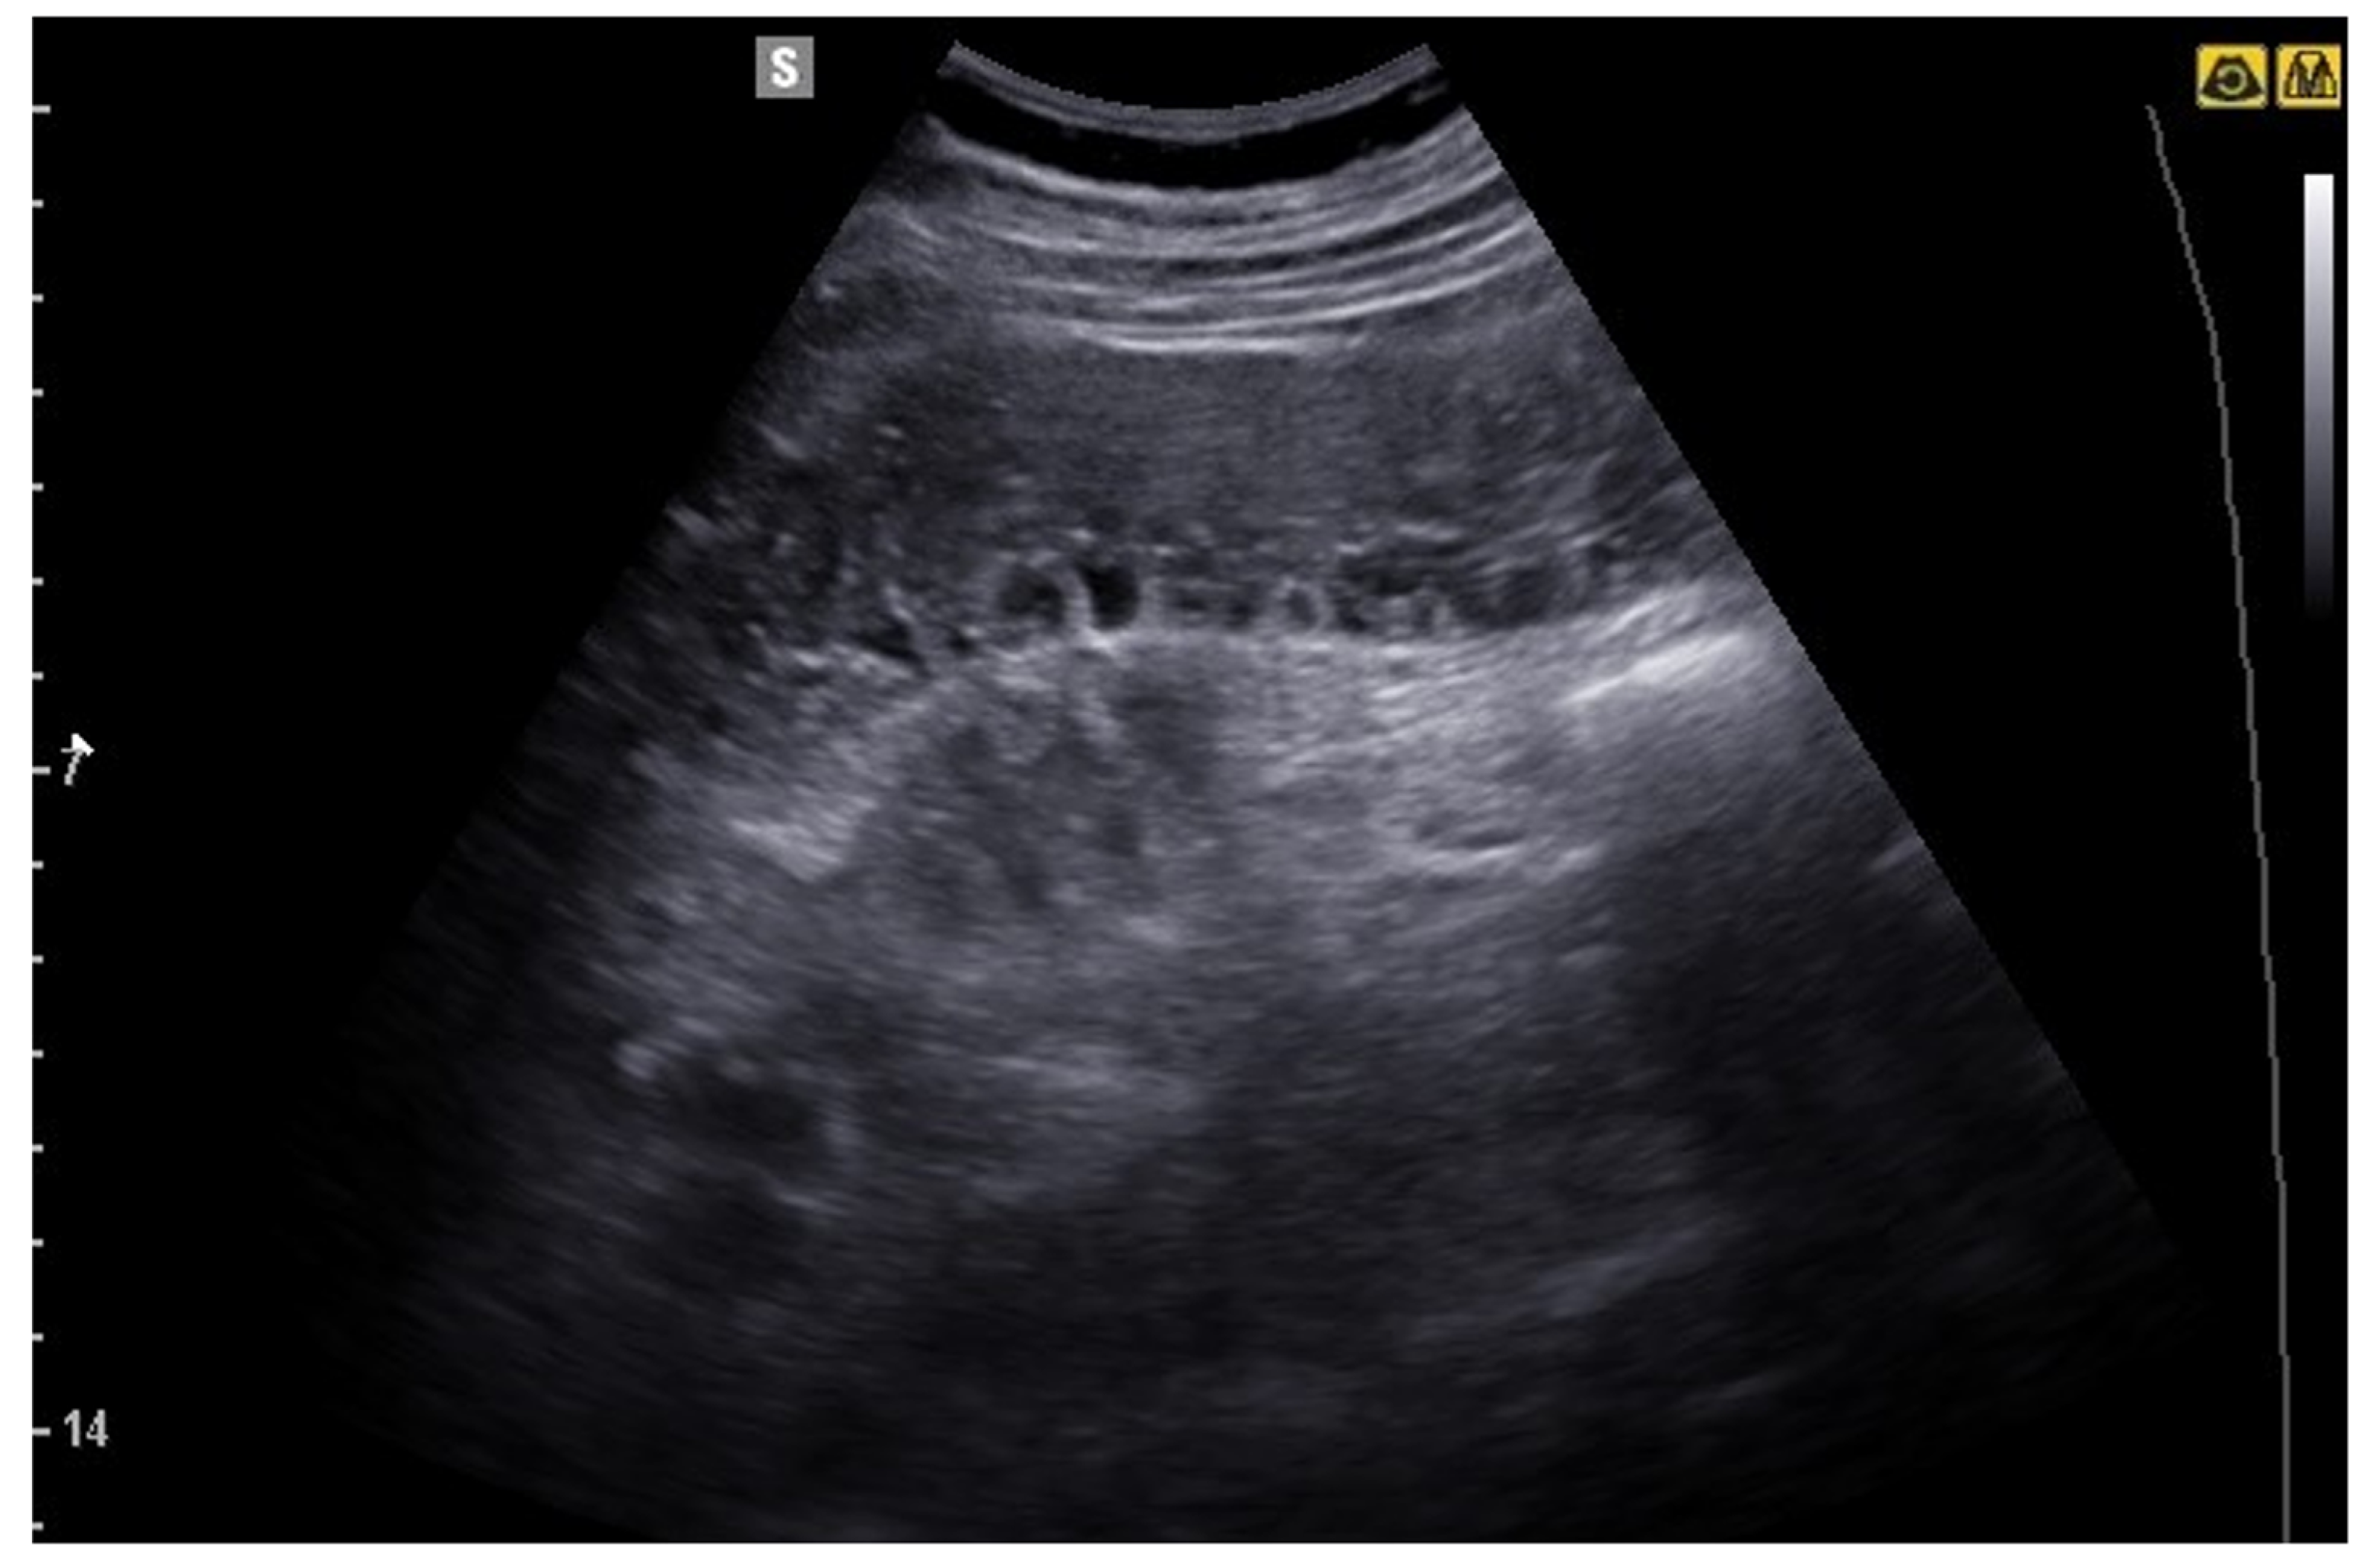

6. Bowel Obstruction

6.1. GIUS Signs of SBO

- Hollerweger, A.; Wüstner, M.; Dirks, K. Bowel Obstruction: Sonographic Evaluation. Ultraschall Med. 2015, 36, 216–235, quiz 36-8. [Google Scholar] [CrossRef]

- Tamburrini, S.; Serra, N.; Lugarà, M.; Mercogliano, G.; Liguori, C.; Toro, G.; Somma, F.; Mandato, Y.; Guerra, M.V.; Sarti, G.; et al. Ultrasound Signs in the Diagnosis and Staging of Small Bowel Obstruction. Diagnostics 2020, 10, 277. [Google Scholar] [CrossRef] [PubMed]